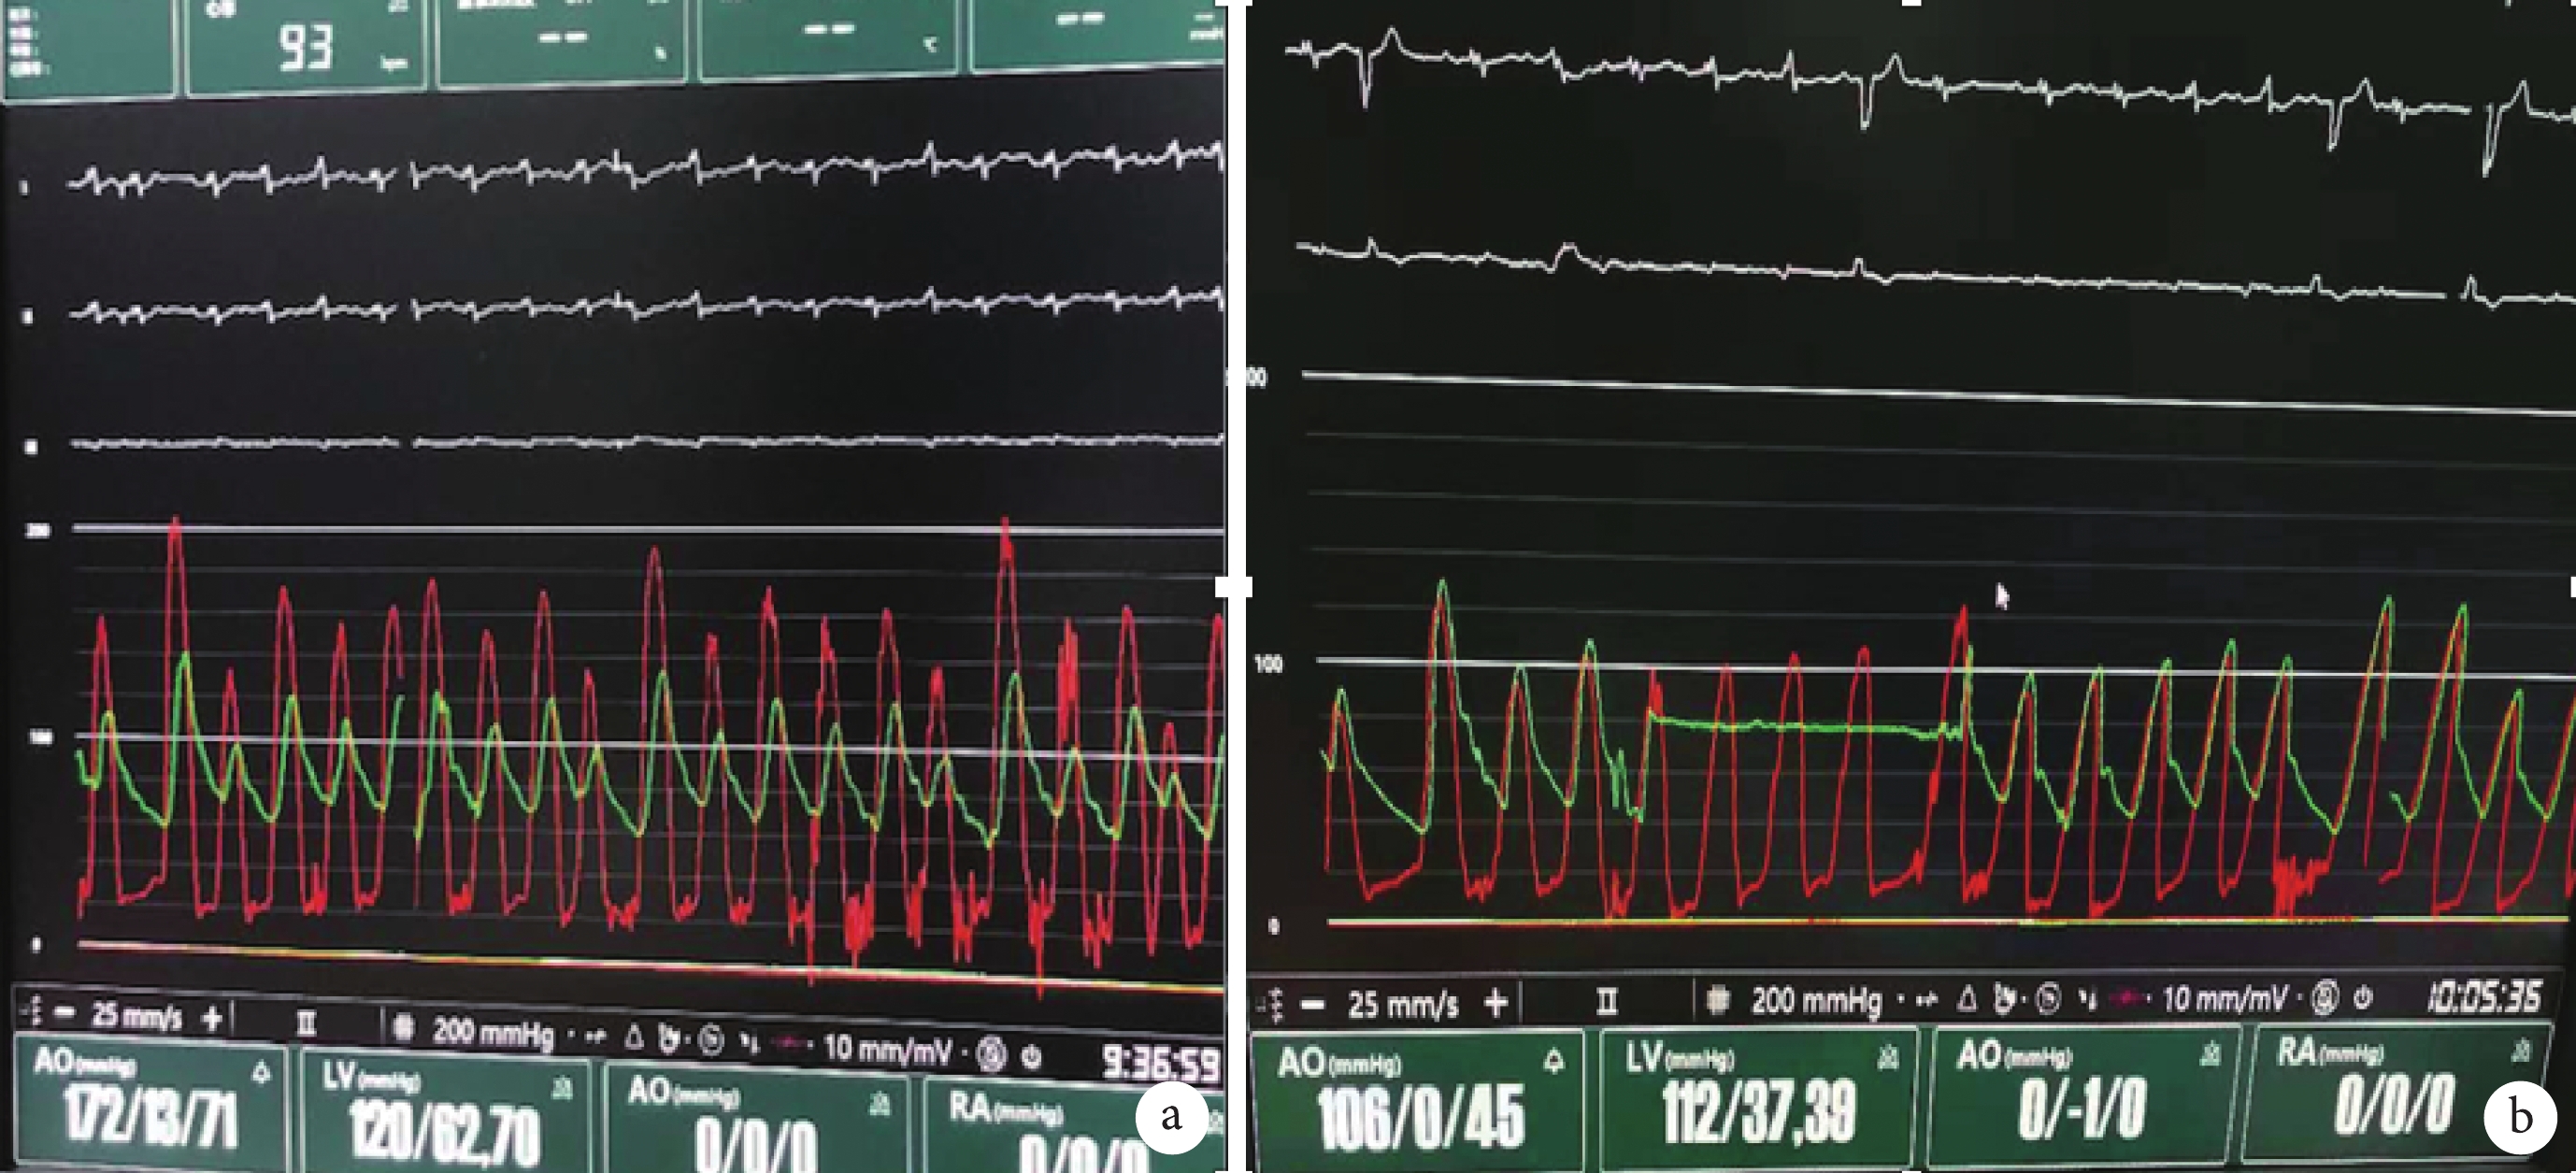

2019 年 10 月 10 日 8 時開始手術。手術過程:根據主動脈 CTA,選擇左側股動脈為主入路。給予靜脈麻醉后行氣管插管成功,同時給予超聲指導下左側股動脈神經阻滯下麻醉,建立右橈動脈有創壓力監測通道。同時建立右側頸內靜脈下行中心靜脈置管。行 TEE,測量患者術前數據,測得 LVEF 為 19.7%(圖 2)。雙側腹股溝區、下腹部前胸部常規消毒、鋪巾。于左右股骨頭骨性標志透視下沿股動脈走行穿刺后,分別先后送入 4F、6F 股動脈鞘管。經右側股動脈鞘管,經 0.035 英寸 J 型導絲(直徑 0.89 mm)送入 6F 彎頭豬尾導管至升主動脈監測中心動脈壓力并協助瓣膜定位。行右側股靜脈穿刺,置入 6F 動脈鞘放置臨時起搏器于右心室心尖部。左側股動脈 Proglide 預縫合,更換 10F 鞘管,AL2 導管指引下直頭導絲跨瓣,沿導絲送入 AL2 導管至左心室,交換為 6F 豬尾導管,主動脈和左心室測壓。經豬尾導管換 COOK TSMG 加長加硬導絲,調整導絲處于左心室滿意位置,退出豬尾導管,經導絲換為 19F 鞘。根據術前 CT 測量結果,選擇 Venus-A 29 mm 瓣膜。經鞘管送入 Venus-A 29 mm 瓣膜輸送系統至主動脈瓣環處,行主動脈根部造影,調整輸送鞘位置,使瓣膜的深度剛好在主動脈瓣瓣環水平,擬 0 位釋放,然后固定輸送鞘,起搏器未起搏,開始釋放瓣膜(圖 3a)。當確認瓣膜處于理想位置后,完全釋放瓣膜(圖 3b)。退出主動脈瓣膜輸送系統;豬尾導管行主動脈根部造影顯示:人工瓣膜位置合適、開合良好,冠狀動脈開口未受影響。瓣膜釋放后 TEE 示瓣膜位置良好,輕度瓣周漏,中心微量反流,無心包積液,前后即刻 TEE 顯示跨瓣壓差較術前明顯改善(圖 4)。血流動力學監測顯示術后跨瓣壓差接近 0 mm Hg(圖 5)。術中患者透視下心臟收縮乏力,血壓低,給予較大量升壓藥物維持,血流動力學相對穩定,瓣膜釋放后血壓 120/80 mm Hg,心率 95 次/min 左右,為房顫心律,未見房室傳導阻滯。造影提示雙側股動脈未見滲血及夾層,退出鞘管、導絲。左右側股動脈均予 Proglide 縫合器縫合。包扎雙側術區。術中共用造影劑 120 mL。手術結束。患者脫機后呼吸偏弱,血氧飽和度略低,帶氣管插管,抱球呼吸下送回心臟監護病房。

a. 術前;b. 術后。紅色為左心室內壓,綠色為升主動脈壓